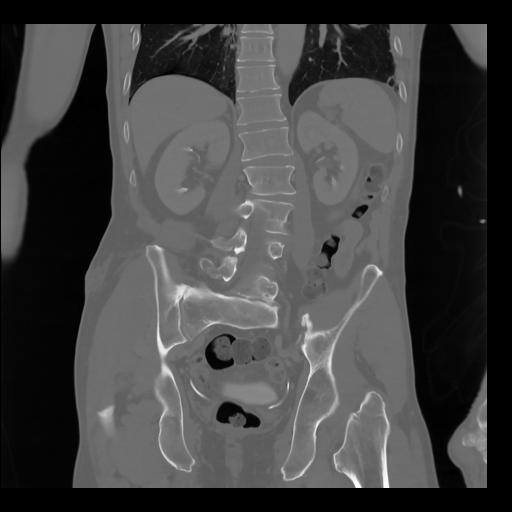

35 CUERPO,CE,Coronal,3.000,CUERPO,Coronal,